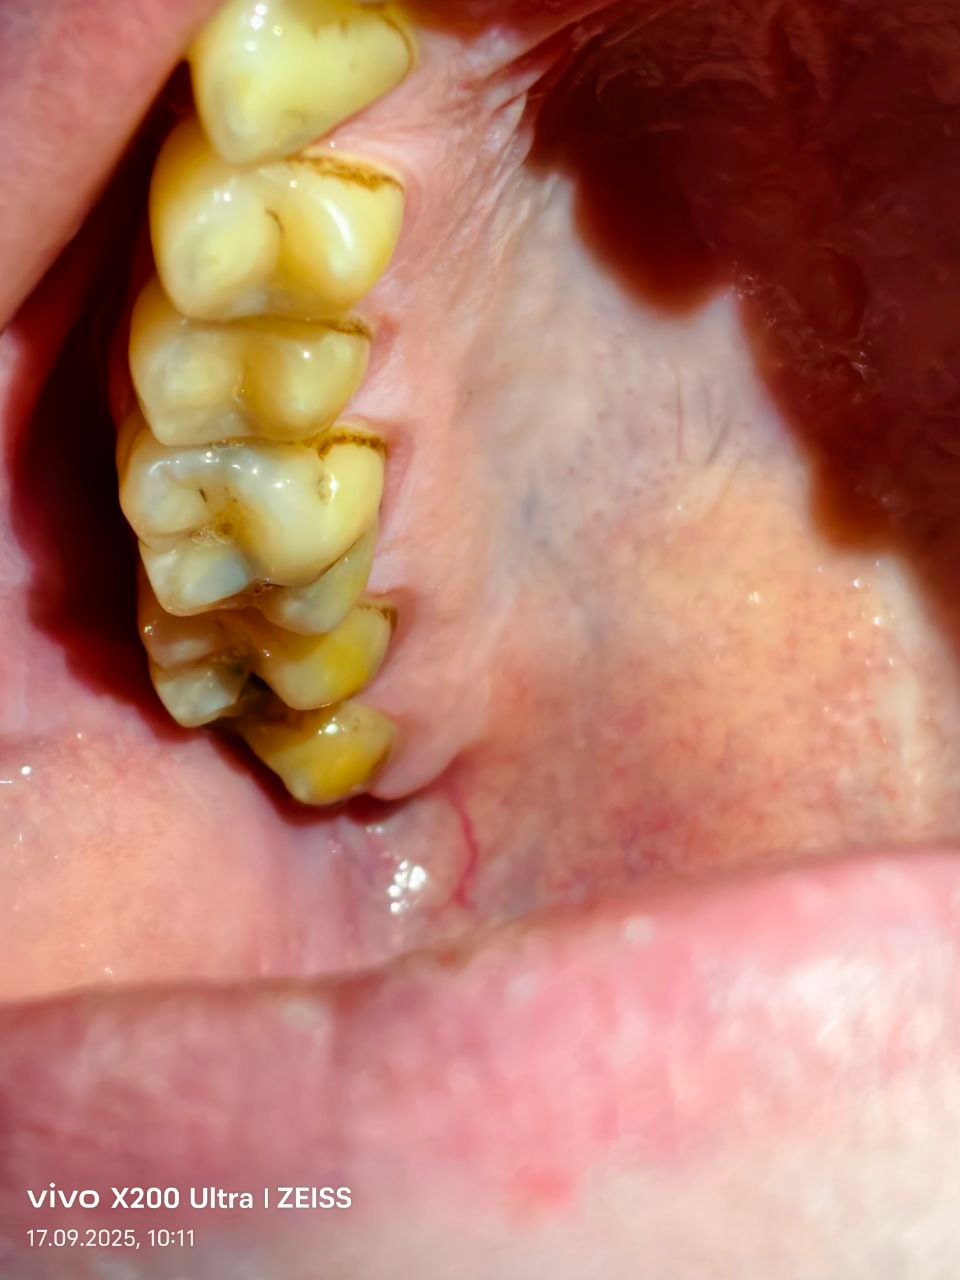

image.png

Аноны, которые лечили, удаляли зубы по ОМС или в частной клинике.

Расскажите почему и в чем был выбор и главный вопрос, сколько денег вы потратили?

У меня 3 дня назад сильно болел зуб снизу и сверху, оба дырявые (который на пикриле 13 назад стояла пломба, 11 лет назад выпала)

сейчас ощущение что они мягкие (правой частью рта не жую)

сейчас боль по меньше, думаю периодонтит, ну и кариес. Сколько в частной клинике выйдет лечение такой хуйни? плюс если коронки ставить.

На пике верхние зубы еще норм. Да и на нидних только один скошенных удалять, остальные восстановить можно

Аноним 11/12/25 Чтв 15:14:24 #43 №327552307

IMG20251211151004.jpg

IMG20251211151300.jpg